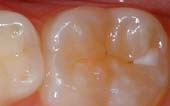

Seal Out Decay

A sealant is a protective coating that is applied to the chewing surfaces (grooves) of the back teeth (premolars and molars), where four out of five cavities in children are found. This sealant acts as a barrier to food, plaque and acid, thus protecting the decay-prone areas of the teeth.

Your pediatric dentist may also recommend protective sealants or home fluoride treatments for your child. Sealants can be applied to your child’s molars to prevent decay on hard to clean surfaces